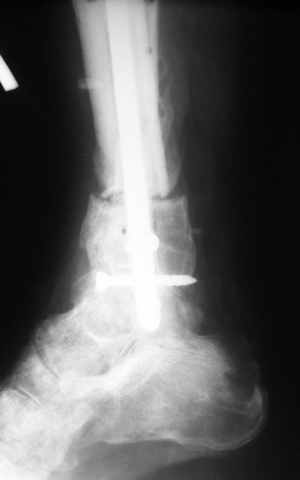

Ерсин, мы тоже имеем опыт такой фиксации. Подобную операцию за последние 3 года мы сделали трем пациентам. Снимки одного из них я прилагаю. К сожалению, ни в одном из этих 3-х случаев мы не получили удовлетворяющего нас результата. Очень трудно провести штифт, введенный антеградно ровно по центру таранной кости. Отсутствие подвижности между диафизом и дистальным отломком большеберцовой кости (после фиксации в аппарате в течение 1-2 мес) очень усложняет проведение штифта в центр блока таранной кости. Поэтому мы от этого пока отказались, и проводим штифт через пятку. При данном варианте фиксации подобных проблем не возникало ни разу.

Вложение не в текстовом формате было извлечено…

Имя     : 4.jpg

Тип     : image/jpeg

Размер  : 18102 байтов

Описание: отсутствует

Url     : http://weborto.net:8080/pipermail/ortho/attachments/20081209/5d3bc875/attachment-0007.jpg